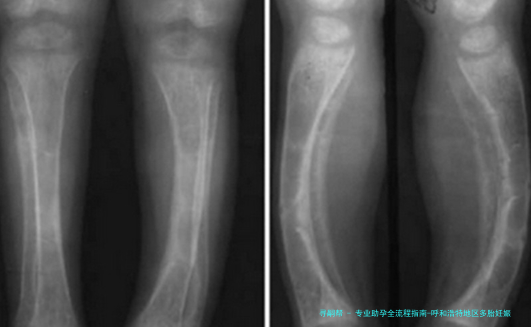

对胎儿来说,多个胎儿妊娠明显增加流产风险(提高5-10倍),导致低出生体重、发育迟缓等问题的发生率明显增高。早产儿各器官发育未成熟,易出现呼吸窘迫综合征、新生儿颅内部出血等多种并发症, *** 妊娠早产儿的死亡率约为单胞胎未足月产儿的2-12倍。

| 胎儿发育风险 | 早产、低体重、生长受限 | 减胎术、营养支持、卧床休息 | 超声监测生长发育 | 定期产检评估 | 早产风险增加5-10倍 |